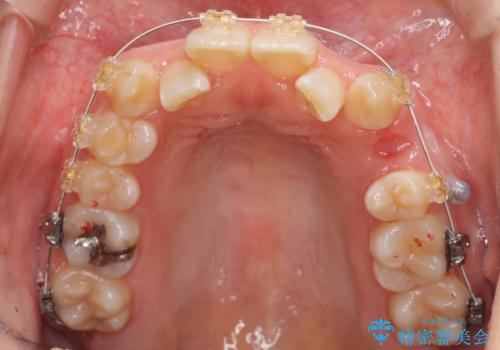

よくある悩み 前歯が裏に2本入っているのを治したい

- 前歯が2本裏に入ってしまっているのを治したいとのことでした。

プラン1:上の正中をずらさない・・・上下左右4本抜歯

プラン2:上の正中は少し左にずれる・・・左の上下2本抜歯

を提案し、プラン2を選択されました。

最小限の抜歯により矯正ができたと、喜んでいただきました。